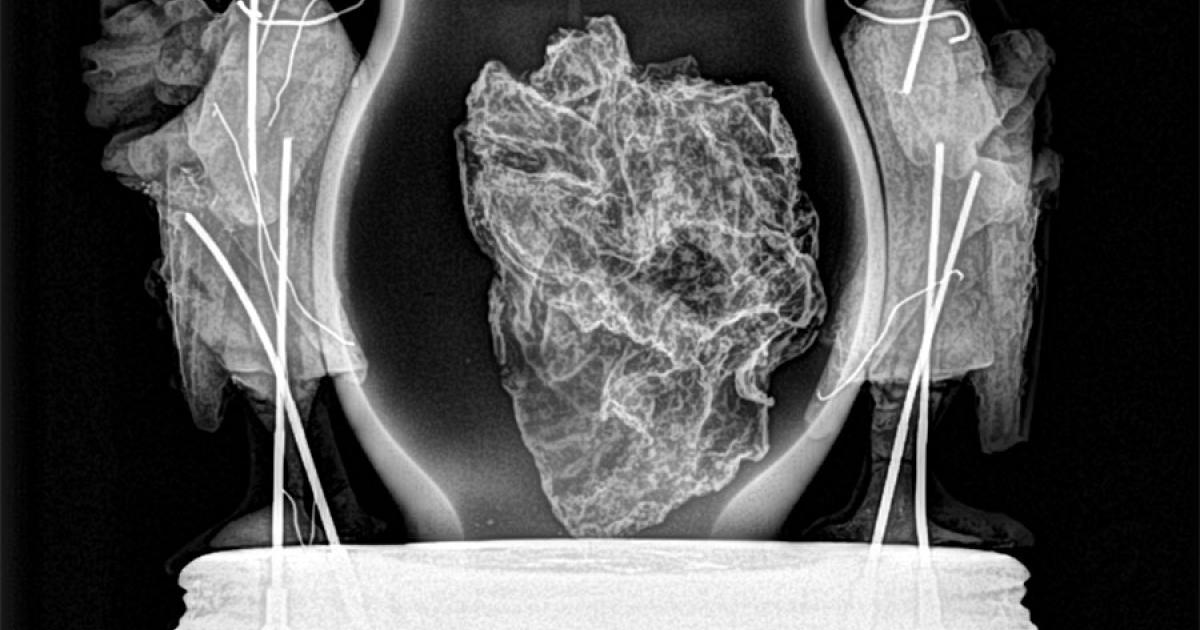

El Servicio de Patrimonio Histórico del Ejecutivo foral ha realizado diversas intervenciones en el corazón de Carlos II de Navarra destinadas a retornar a su lugar los objetos en las mejores condiciones de conservación, aplicar tratamientos de estabilización que garanticen su preservación óptima, y obtener datos para iniciar un proyecto de investigación del conjunto funerario.

En concreto, se han tomado muestras microscópicas de los restos de todos los componentes de las piezas, tejidos, ceras, policromías, madera, así como de los restos biológicos, pólenes, fibras o colonias de hongos incluidas, y del propio corazón para hacer el estudio de ADN y antropológico forense.

Todos los componentes y datos, acompañados de material gráfico, se han puesto en manos de diversas disciplinas para que, cuando las circunstancias lo permitan, se puedan elaborar estudios que ayuden a conocer mejor el proceso de embalsamado, la confección de los recipientes de custodia, las distintas intervenciones que ha sufrido el corazón desde su sepultura inicial el 18 de enero de 1387 hasta la actualidad, y todo aquello que la ciencia permita extraer y aportar al conocimiento del corazón del rey.

También han tomado parte el Departamento de Biología de la Universidad de Navarra que tomó las muestras biológicas; el gabinete ‘Medicis’ que realizó un TAC; Alex Duró que realizó la fotogrametría; la empresa ‘Muraria’ por la revisión documental y la gestión del diseño expositivo; y la empresa Moreno Valles que trasladó la pieza.